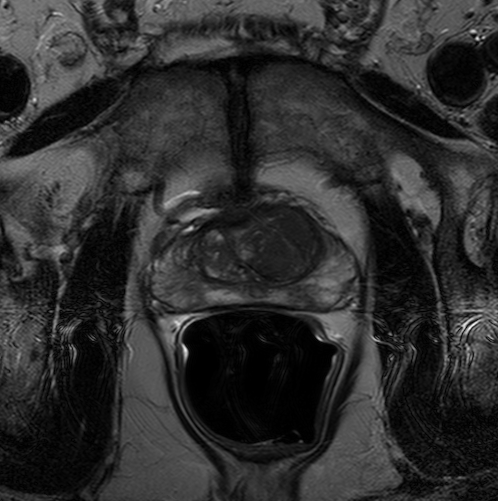

We trained our network on 77 patients. The input images and the manual ground truth annotation are shown in Fig.4. As we have described above, these images were acquired from different patients, and these images include the clinical variability. To evaluate our method, we randomly selected 4 patients with 64 images before training. These images do not take part in training and the prostate has been manually pre-delineated by a radiologist, which were used as the ground truth to evaluate the performance of automatic segmentation. We also selected dice coefficient as the evaluation method[30]. And to validate our method against U-Net and fully convolutional networks (FCNs), we used the same dataset to train and test the U-Net and FCNs.

To intuitively compare the proposed method with U-Net and FCN, the segmentation results of some representative and challenging samples are shown in Fig 5. It can be seen that these prostate images have fuzzy boundaries and the pixel intensity distributions are inhomogeneous both inside and outside of the prostate. Besides, both prostate and nonprostate regions have similar contrast and intensity distributions. All of these phenomenons make the segmentation difficult.